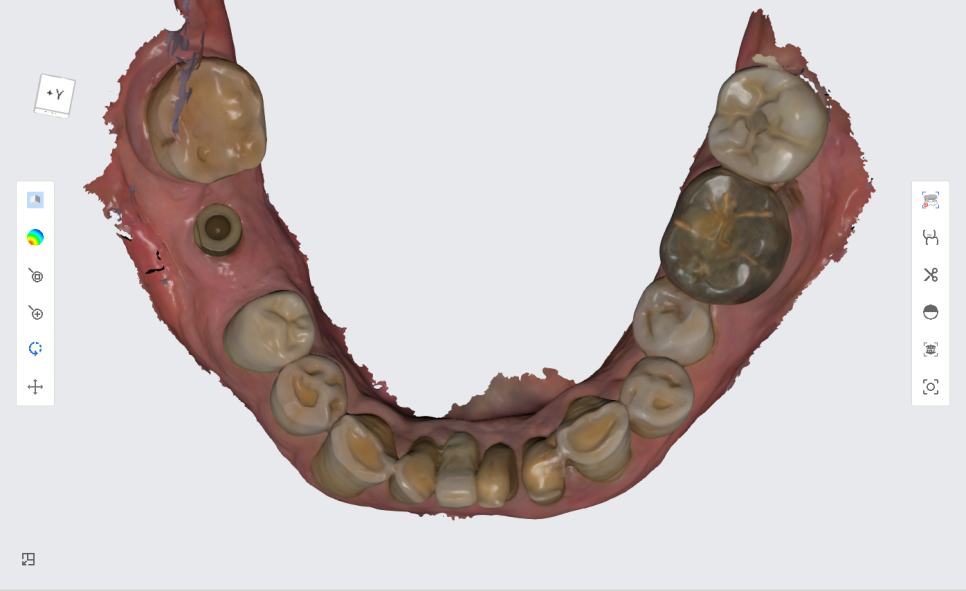

저희 서울바르디치과는 3D 스캐너를 이용하여

본 뜨는 작업을 진행합니다.

컴퓨터 3D 작업을 통해

입안에 찰흙같은 이물질을 넣는 불편감을 최소화하고

더 정교하고 정밀하게 보철 크라운을 제작합니다.

본 뜨는 작업을 진행할 때는

임플란트위에 잠겨져 있던 뚜껑나사를

스캔하는 장치(스캔바디)로 바꾸어서 3D 스캔을 진행 한 다음

다시 원래대로 입안에 있던 뚜껑나사로 연결 해드립니다.